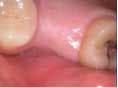

A 53-year-old female with a medical history of hypothyroidism, seasonal allergies, and asthma taking Synthroid and Singula presented to my office with pain in No. 3, failed root canal therapy, and a fracture. The tooth was deemed hopeless and extraction and implant placement was treatment planned. Under local anesthesia, tooth No. 3 was sectioned into three pieces and extracted. The sockets were debrided, filled with gel foam, and closed with chromic gut sutures. Healing was uneventful. The patient did not return for two years for follow-up. A CT scan was taken, which confirmed that approximately5 mm of bone remained below the floor of the sinus. After reviewing the options with the patient, a treatment plan of an internal sinus lift (osteotome), bone graft, platelet-rich fibrin (PRF) and simultaneous implant placement was agreed upon. Under local anesthesia, a full thickness flap with two vertical releasing incisions was performed at tooth No. 3 site. A trephine bur was used to a depth of 4 mm. An osteotome was then employed to infracture the bone core, which remained attached to the Schneiderman membrane. A bone graft consisting of DFDBA, anorganic bovine bone, and PRF was used in the osteotomy to increase the vertical bone height using sequential osteotomes. After sufficient elevation, a 7x9 tapered implant was placed on low speed to 50% of the implant depth. The remaining placement of implant was done with a hand torque on 50 ncm to allow for further expansion of the alveolar housing. A healing abutment was placed using the principles of platform switching. Healing was uneventful, and integration was successful.

Case 1: Implant and osteotome bone graft through the socket with Southern Implant